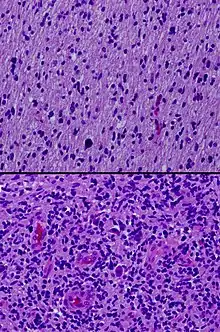

Hematoxylin and eosin stains from different sections of a single diffuse intrinsic pontine glioma specimen, showing low-grade (top) and high-grade (bottom) areas.

In pathology, grading is a measure of the cell appearance in tumors and other neoplasms. Some pathology grading systems apply only to malignant neoplasms (cancer); others apply also to benign neoplasms. The neoplastic grading is a measure of cell anaplasia (reversion of differentiation) in the sampled tumor and is based on the resemblance of the tumor to the tissue of origin.[1] Grading in cancer is distinguished from staging, which is a measure of the extent to which the cancer has spread.

Pathology grading systems classify the microscopic cell appearance abnormality and deviations in their rate of growth with the goal of predicting developments at tissue level (see also the 4 major histological changes in dysplasia).

Cancer is a disorder of cell life cycle alteration that leads (non-trivially) to excessive cell proliferation rates, typically longer cell lifespans and poor differentiation. The grade score (numerical: G1 up to G4) increases with the lack of cellular differentiation - it reflects how much the tumor cells differ from the cells of the normal tissue they have originated from (see 'Categories' below). Tumors may be graded on four-tier, three-tier, or two-tier scales, depending on the institution and the tumor type.